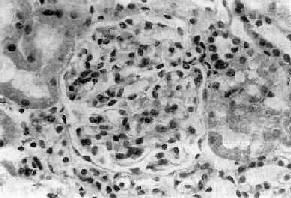

4.腎臟活檢光鏡檢查正常或輕度異常,腎小球系膜呈輕度至中度增生免疫螢光陰性,電鏡下只有瀰漫性GBM變薄而無電子緻密物沉積,這也是本病惟一的或最重要的病理特性。正常基膜寬度為300~400nm而在本病基膜寬度僅為150~225nm,最薄的腎小球基膜為110nm,為正常人的1/3~2/3。根據以上要點薄基膜腎病診斷可成立。

1.光鏡檢查 通常無異常發現光鏡下腎小球一般正常,腎小管記憶體在紅細胞管型。偶爾可見一些非特異的輕微腎小球變化,如輕度系膜增生,並無診斷意義也有一些報導發現球性腎小球硬化、灶性小管萎縮、輕微系膜增寬和不成熟腎小球。

3.超微結構 主要超微結構特點是腎小球基底膜變薄。電鏡下可見到本病特徵性改變——瀰漫性GBM變薄,GBM厚度僅為正常厚度的1/3~2/3甚至更薄並無增厚劈裂的GBM節段出現。在有些家族中個別成年患者腎小球基底膜厚度正常,而家族的其他成員腎小球基底膜變薄。在一些表現為家族性良性血尿的家族,腎小球基底膜厚度正常。即使在存在腎小球基底膜變薄的家族,並非所有的血管襻管壁都變薄在所有年齡的本病患者都可發現系膜旁的增厚,和局灶性毛細血管壁破裂有關。在少數病例可發現血管輪廓節段性不規則及系膜顆粒狀物質沉積。